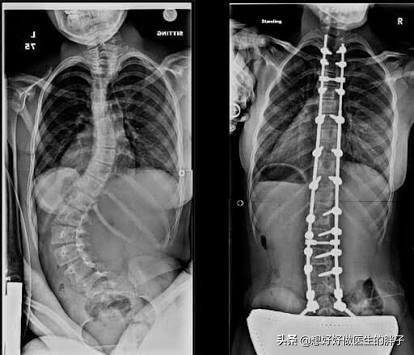

下面是一例典型脊柱侧弯的孩子查体和片子的对比照片:

如果高度可疑脊柱侧弯,请记住无论是否出现疼痛都需要去医院检查x线,要挂骨科号或者是脊柱专科号。一般医生会给与进行脊柱全长的x线检查明确诊断。医生会根据孩子的片子判断是否存在脊柱侧弯,如果存在侧弯,医生要测量一个侧弯的角度,称之为cobb角,如果<25°可以采取支具保守治疗,在25°至45°之间需要考虑手术治疗。